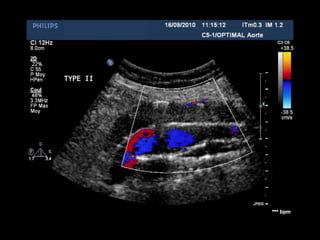

ENDOFUITE TYPE 2

TYPE 2TYPE 2

ReperfusionReperfusion parpar

circulation rcirculation réétrogradetrograde

(branche(s) de l(branche(s) de l’’aorteaorte

native)native)

ArtArtèère lombaire,re lombaire,

mméésentsentéérique infrique inféérieure,rieure,

iliaque interneiliaque interne

ENDOFUITE TYPE 2 TYPE2TYPE 2 ReperfusionReperfusion parpar circulation rcirculation réétrogradetrograde (branche(s) de l(branche(s) de l’’aorteaorte native)native) ArtArtèère lombaire,re lombaire, mméésentsentéérique infrique inféérieure,rieure, iliaque interneiliaque interne Type 2 Mésentérique inf.